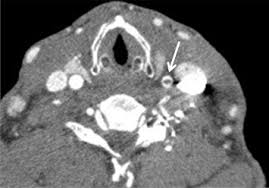

Carotid artery dissection is a tear in one of the layers of the artery wall. Spontaneous dissection of the carotid artery occurs in 3 per 100,000 of the population annually (1). The natural history of cerebrovascular fmd is unknown and management of symptomatic patients can be challenging. Blood vessel walls normally have three layers, and a tear in any of these can allow blood to flow into the resulting space, causing the vessel to bulge. Carotid artery dissection is a major cause of cerebral infarction in the young. Carotid artery dissection has been described after chiropractic manipulation. May occur spontaneously, or in the setting of major/minor neck trauma (mvc (classically a seat belt injury)) vs. Scad can slow or block blood flow to the heart, causing a heart attack, abnormalities in heart rhythm or sudden death.

The natural history of cerebrovascular fmd is unknown and management of symptomatic patients can be challenging. A carotid dissection is a tear in the inner layer of the wall of a carotid artery that allows bleeding into the artery wall. Internal carotid artery (ica) dissection, like arterial dissection elsewhere, is a result of blood entering the media through a tear in the intima 1 and is a common cause of stroke in younger patients. Carotid artery dissection has been described after chiropractic manipulation. It can involve a carotid or vertebral artery and sometimes multiple arteries can be involved.

Arterial dissection is a tear of the inside of the artery. The tear that initiates the dissection may occur spontaneously or after injury. Medical imaging tests can help rule out other conditions with similar symptoms. The first portion of each carotid artery is the called the common carotid artery. These arteries supply blood to your brain. May occur spontaneously, or in the setting of major/minor neck trauma (mvc (classically a seat belt injury)) vs. Similarly, dissections affect distal parts of the extracranial vertebral artery, whereas atherosclerosis tends to involve the proximal segments C0338585) spontaneous or traumatic separation of the layers of the carotid artery wall. Carotid dissection is a tear in the carotid artery wall. But it's still a dangerous situation. I will elaborate in a few sentences. Blood vessel walls normally have three layers, and a tear in any of these can allow blood to flow into the resulting space, causing the vessel to bulge. It manifests with headache, neck pain, temporary vision loss, and/or ischemic stroke.